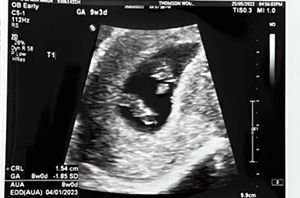

Took the test kit again today and saw this “faint line” became darker. I’m using the guardian test kit, can anyone confirm if there’s a chance this is a false positive?

Post reply image